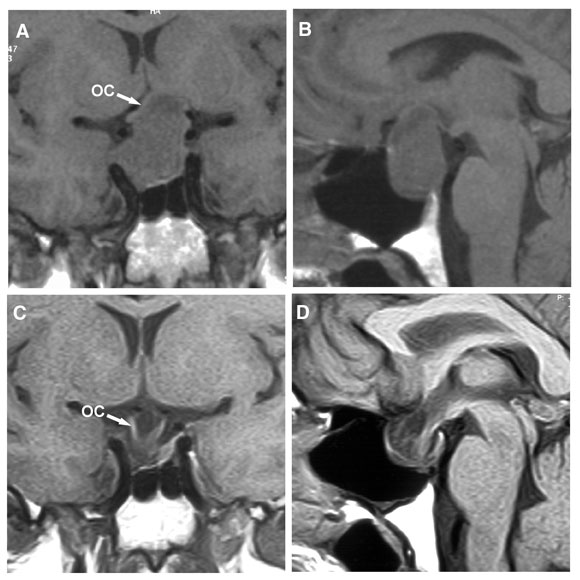

6: Large prolactinoma before and after cabergoline therapy

Magnetic resonance imaging in a 47-year-old man who presented with bitemporal visual field loss. (A, B) Before treatment with cabergoline, showing a large mass expanding the pituitary fossa, with substantial suprasellar extension elevating the optic chiasm (OC). (C, D) 6 months after starting cabergoline therapy (0.5 mg twice weekly), showing marked shrinkage of the mass, which is now entirely within the pituitary fossa, and decompression of the optic chiasm, which has descended into the fossa. The patient’s vision improved within a week of starting cabergoline. After 3 weeks, visual fields were almost normal, and serum prolactin level had fallen from 39 000 mU/L to 563 mU/L (reference range, < 330 mU/L).